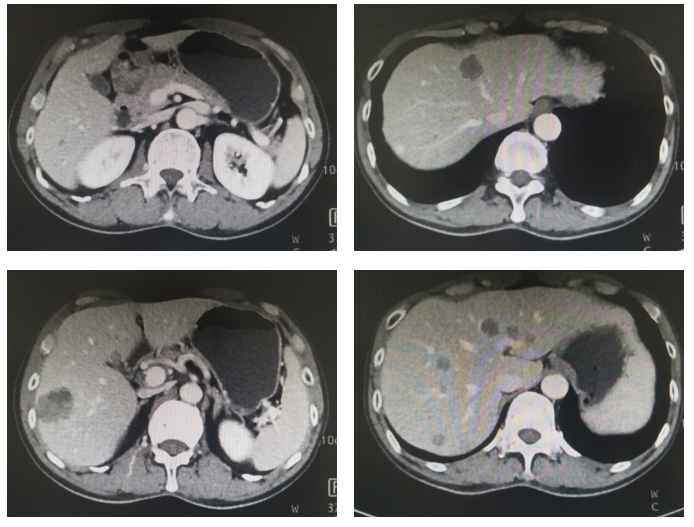

上腹CT:肝内多发低密度结节,胃窦区胃壁增厚(图1)。

评估:治疗后3月和5月复查腹部CT情况(图2和图3).

图3. 腹部CT平扫+强化(治疗后2月,2020年1月)

图4. 腹部CT平扫+强化(治疗后5月,2020年3月)

影像科:根据患者治疗前、治疗后首次及再次复查CT看,原发病灶胃壁增厚明显减轻,肝转移病灶明显缩小,部分病灶消失,首次CT判效PR,再次复查CT确认PR。提示内科治疗有效。

图5. 腹部CT平扫+强化(治疗后7月,2020年5月)